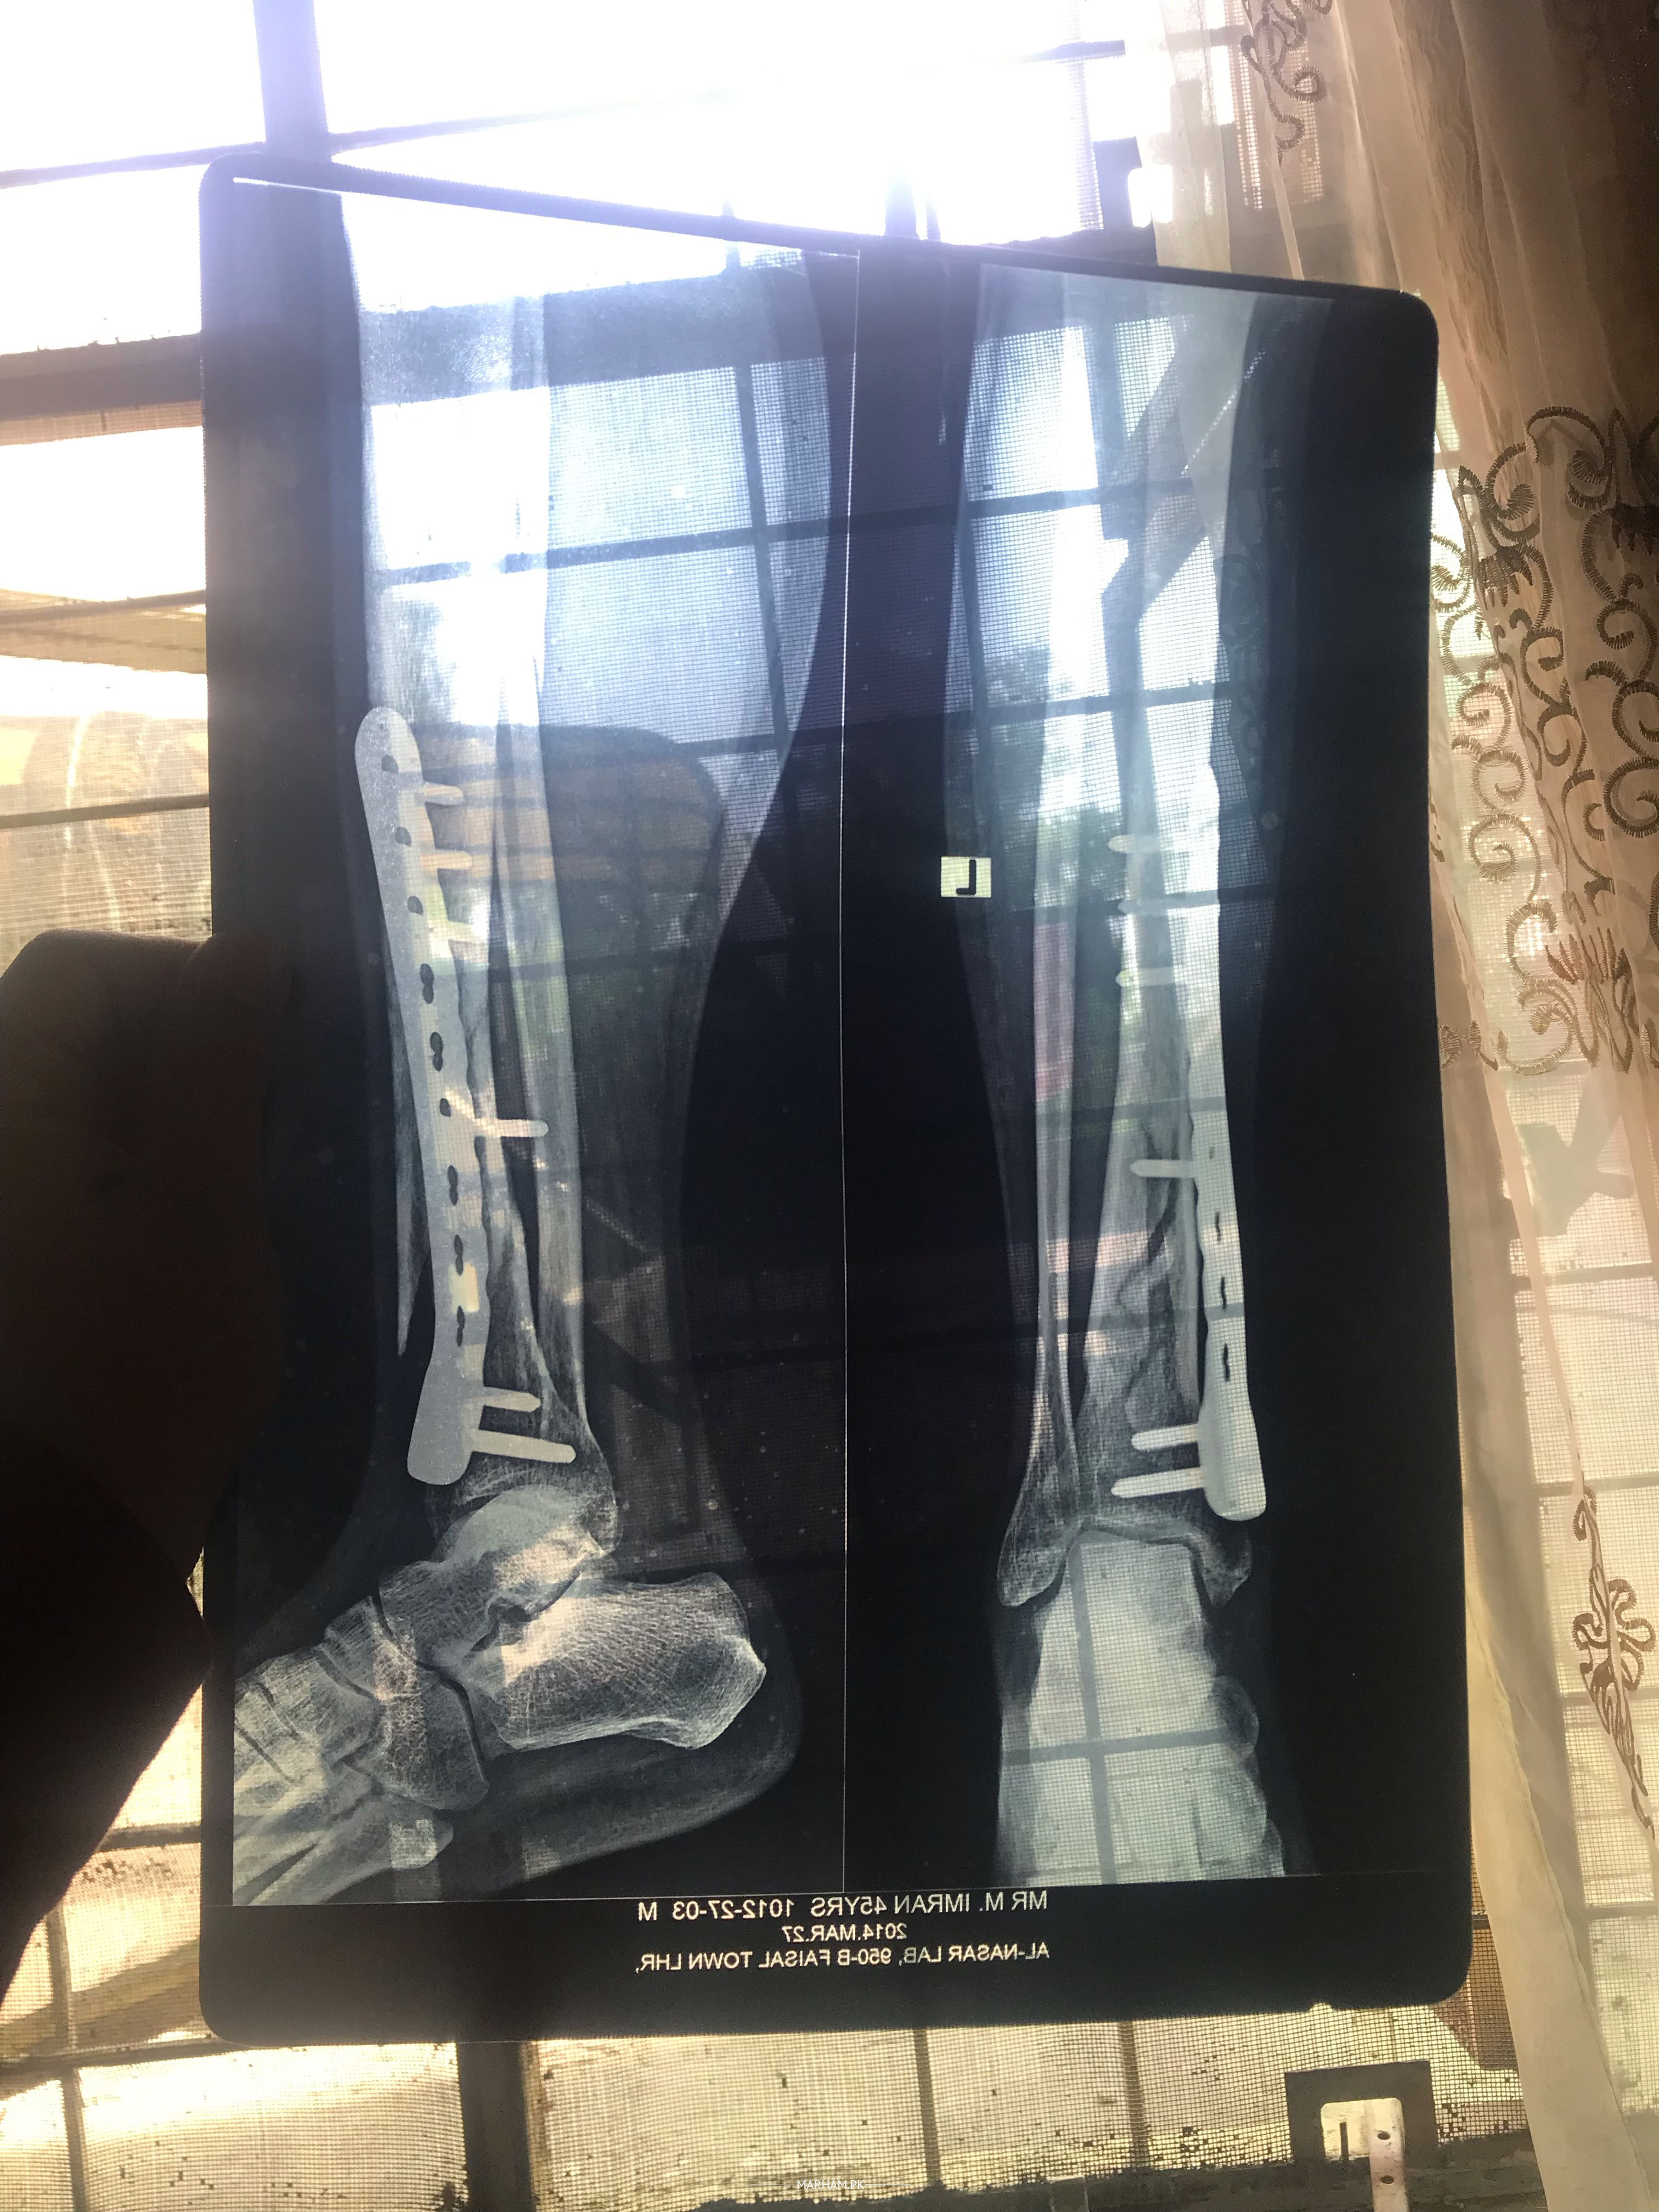

Assalamoalikum Father ki leg ma se plate nikalwai thi maximum 5 months pehle unki pain abhi taq nai gai unko plate nikalne k bad still pain ha pahle b pain thi jiski wjha se plate nikalwai thi plate nikalwane se pain kam hoi ha phle se laqin abhi b still pain ha or father ki health week ho gai ha Kuch suggest kr den Kindly koi medican ya kuch suggest kr den wo Dr k pass jane se bhut ghabraty Allah apko khush rakhy Shukrea Allah hafiz before and after pics and xray b opration se pehle ki or opration k bad ki plates lagne k bad ki b xray lgay ab plates nikal gai ha laqin pain nai ja ray xray clear ha plates nikalne k bad ka xray ki picture available nai wo dr kehty clear ha opration k bad drd chali jani chai laqin abhi taq drd nai gai

Aur fracture kaise hoa ta??? Accident hoa ta ya girh gaey teh??? Unko B. P, sugar ya koi aur bemari tu nahin.. Agar apke pass X-ray hain tu kindly share karen??

Apke father ke X-ray main ne dekain hai. Ye complex fracture ta. 2 bones ka fracture multiple jaga tah.. Unko numbness ya leg sun tu nahin hojate??